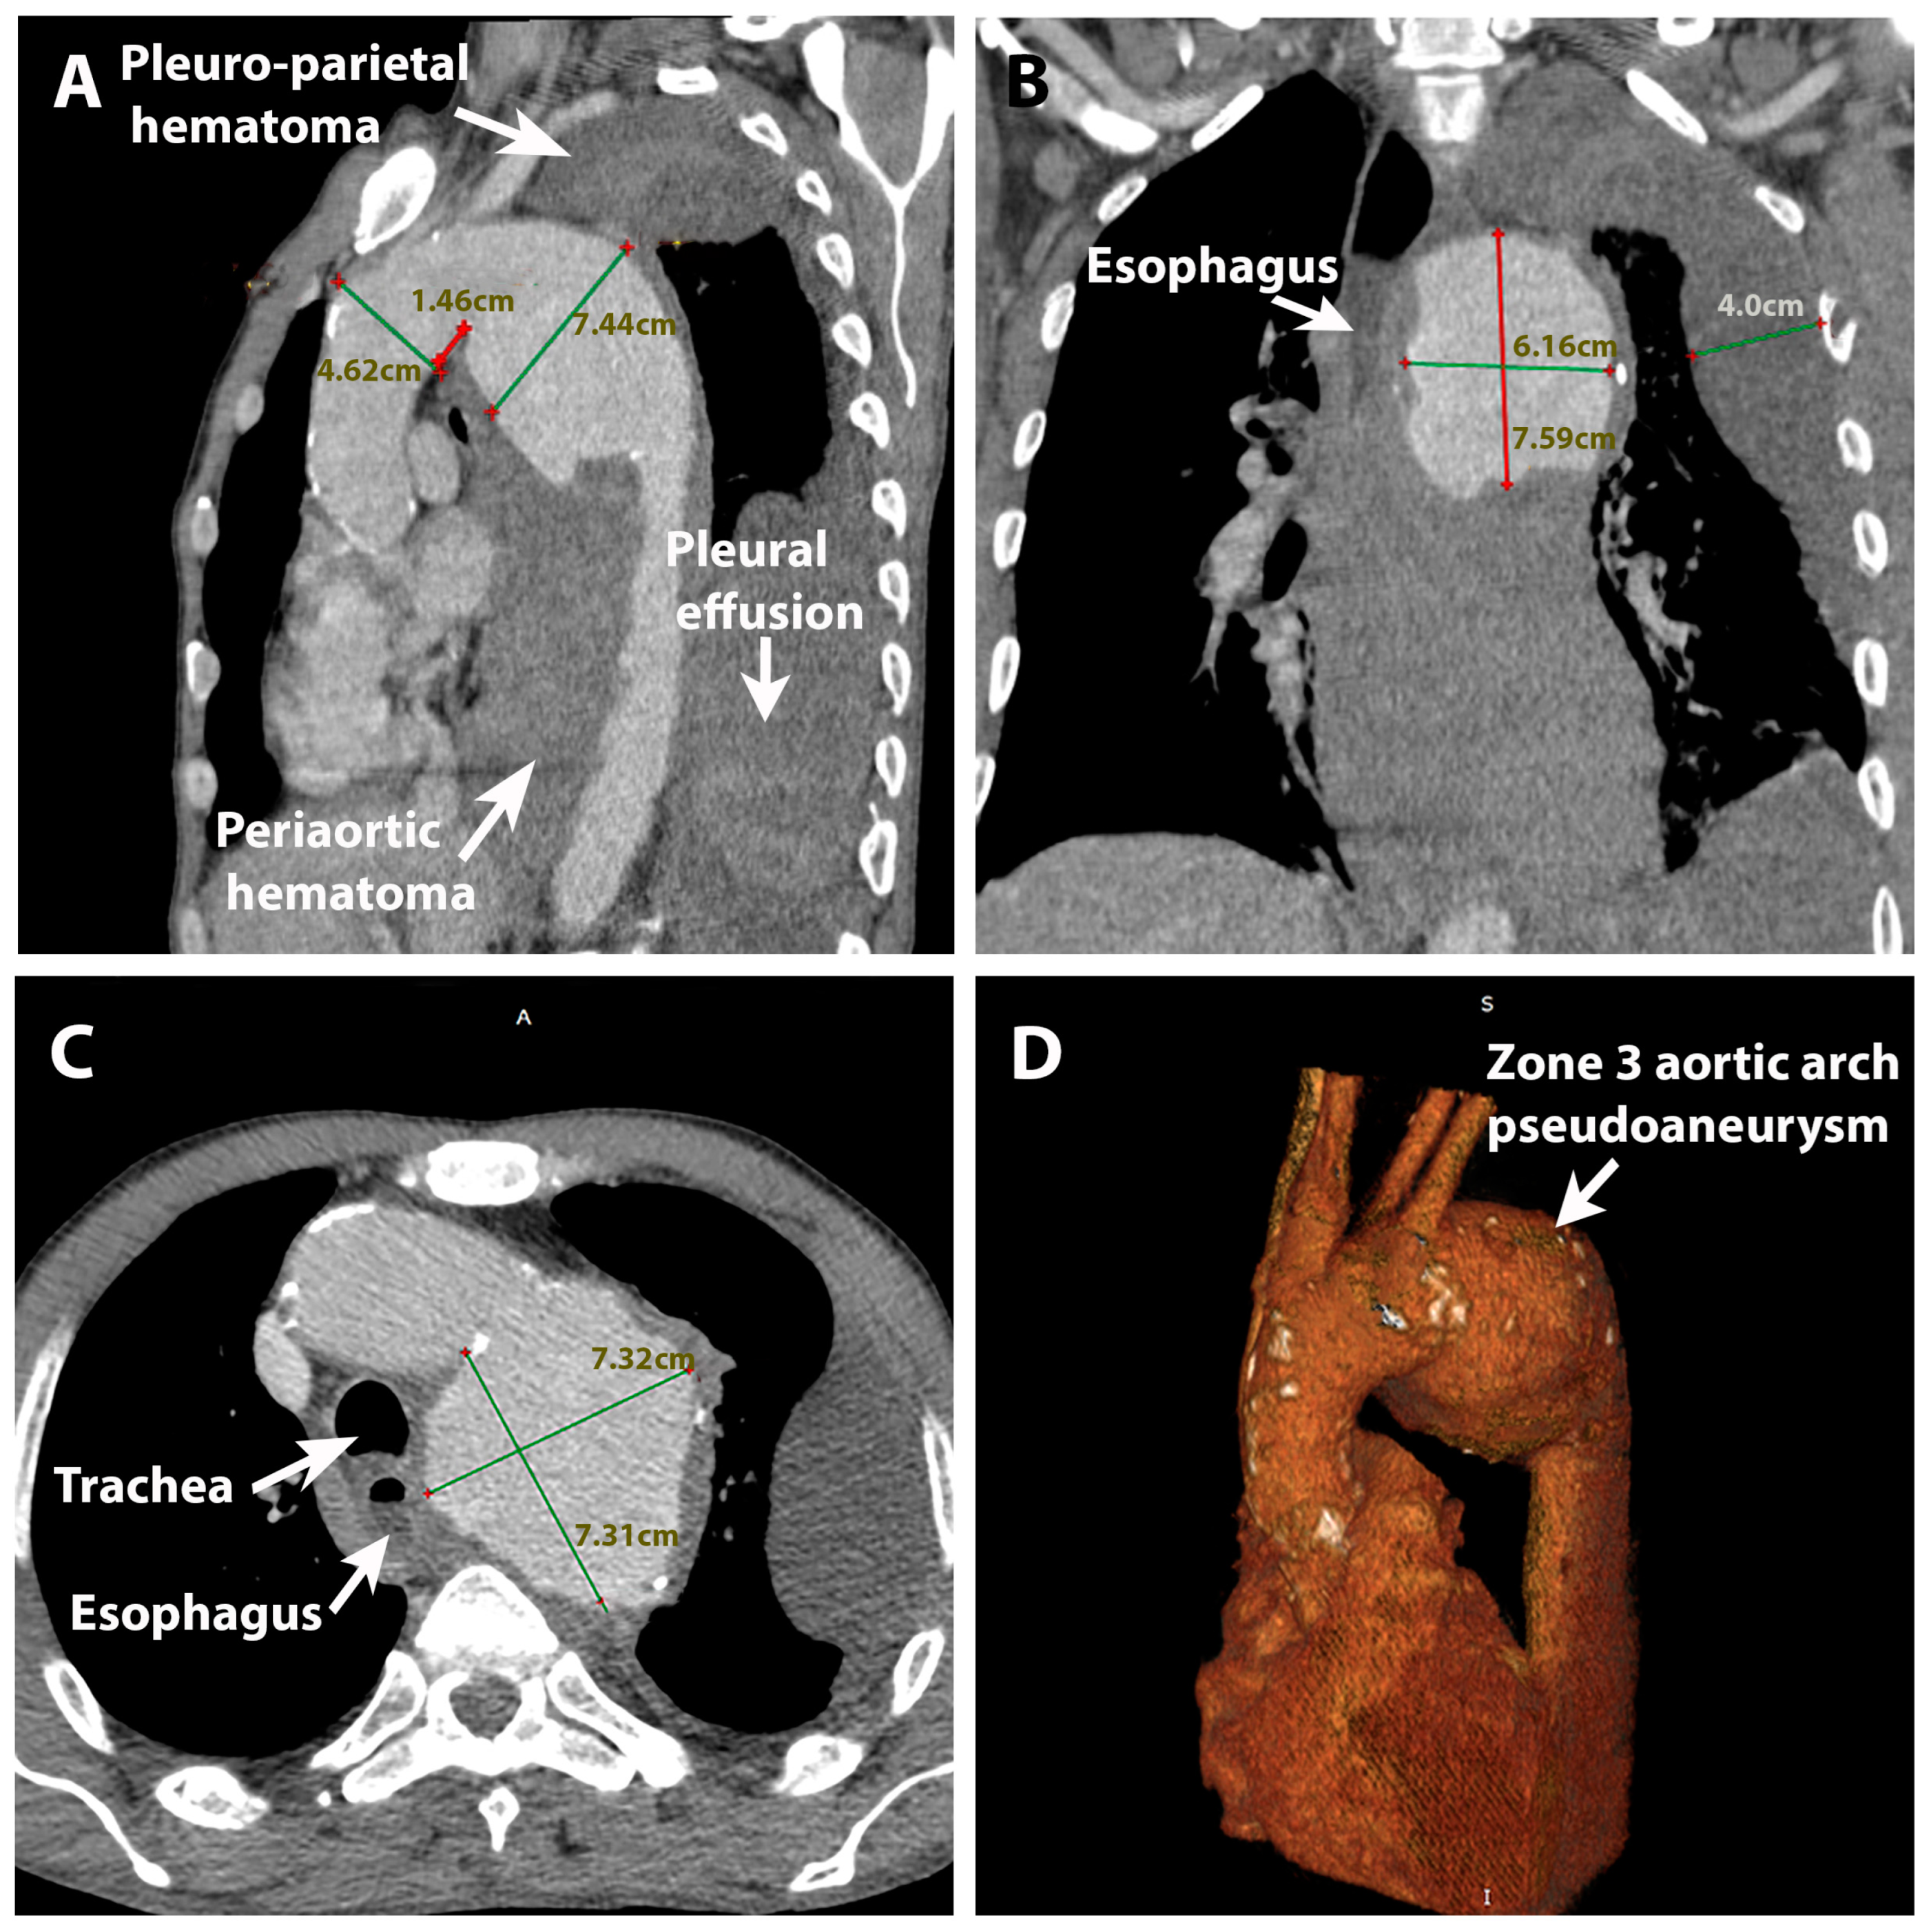

2. Case Presentation